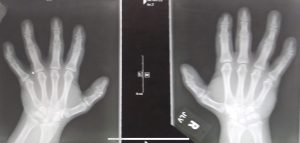

Dr. Nash, who is also a fellow Egyptian by birth and Coptic, is also a music lover and was very much interested by the fact that I was born with a disability in both hands and yet am able to play Rachmaninoff. What got me intrigued in my conversations with Dr. Nash was when he told me that I could help hand surgeons understand more about how someone like me can do what I do despite my hands, and that understanding my story would help them better work with children with unusual hand conditions and their parents.

“We surgeons are of the understanding that unless the hands are in perfect condition, you really can’t do something as complicated and as demanding as what you do,” he remarked.